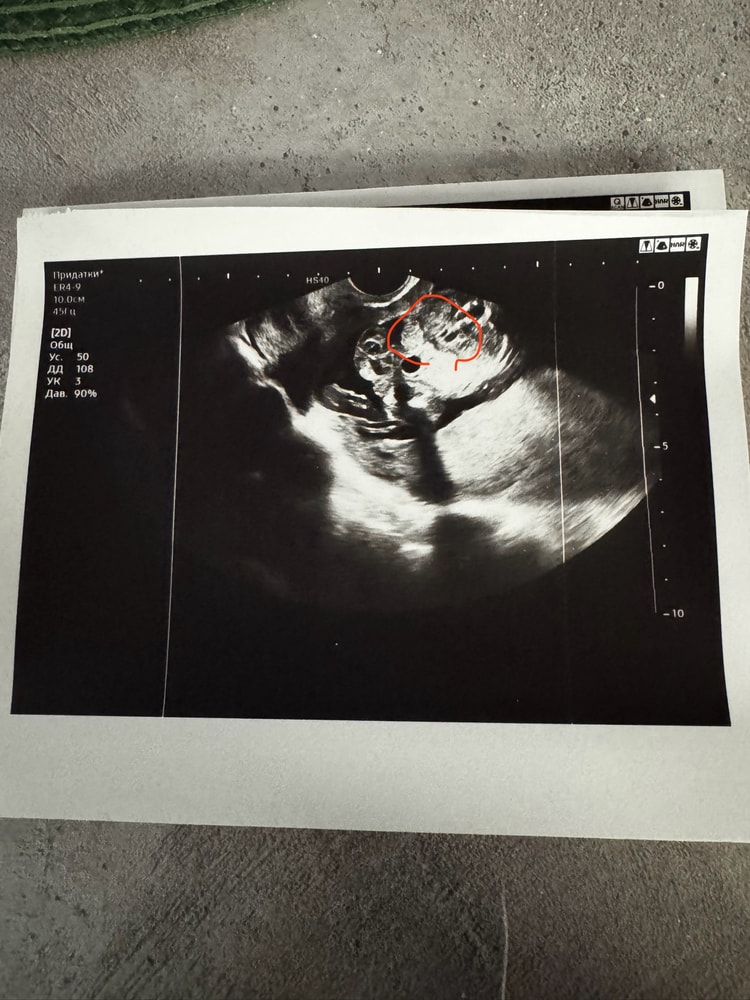

Здравствуйте, девушки! На первом скининге говорили мальчишка. Потом ходили на доп узи в 18 недель, не выдержали перед вторым скринингом сказали уже девочка но тоже не точно, так как сидит на попе на пуповине . Посмотрели вагинально , тоже говорит на девочку похожа. Что вы думаете ?